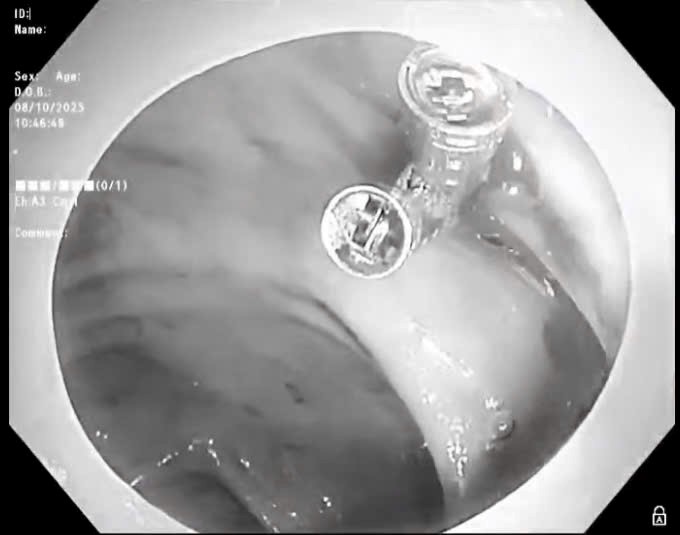

Quảng Trị: Kịp thời cứu cháu bé bị kim chọc tủy rơi vào đường thở

Chủ Nhật, ngày 16/11/2025 08:23Ngày 15/11, Bệnh viện Đa khoa tỉnh Quảng Trị cho biết vừa cấp cứu thành công một cháu bé 3 tuổi bị kim chọc tủy dài 22mm rơi vào đường thở. Dị vật trong đường thở của bệnh...